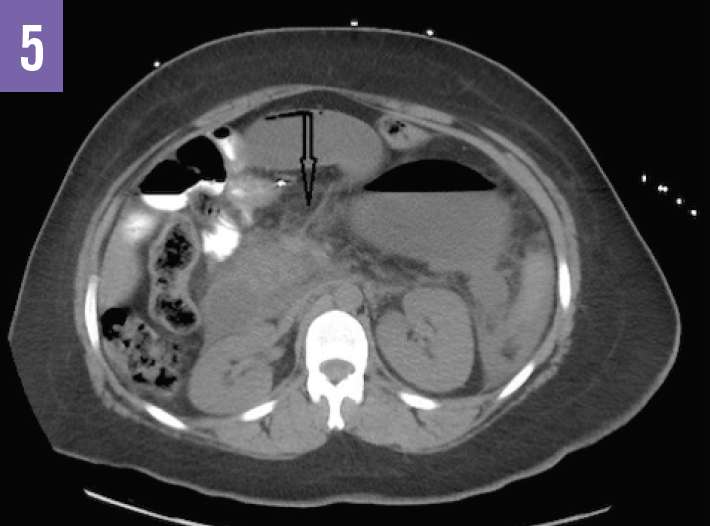

Diagnostic tests. An acute abdominal radiograph series was unremarkable for pneumoperitoneum but demonstrated a gastric air bubble (Figure 1). Computed tomography (CT) of the abdomen and pelvis with oral diatrizoate meglumine and diatrizoate sodium solution contrast medium demonstrated free air under the left hemidiaphragm and gastric pneumatosis (Figure 2), possible obstructions of the bilioenteric limb and within the common channel (Figures 3 and 4), and fat stranding at the pancreatic head (Figure 5).

Based on the imaging results, the patient received a diagnosis of internal hernia with perforation of the gastric remnant.